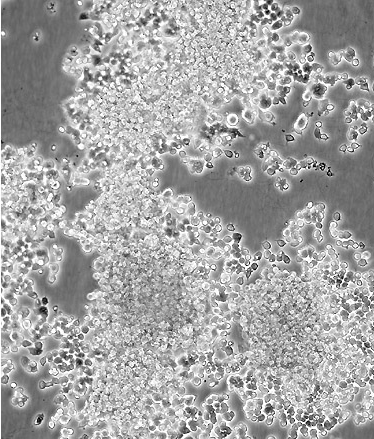

中文名稱 大鼠腎上腺嗜鉻細胞瘤細胞(高分化)

組織來源 腎上腺嗜鉻細胞瘤

細胞種屬 rattus norvegicus, rat

生長特性 adherent

形態特征 polygonal

細胞描述 該細胞系來自能移植的雄性大鼠腎上腺嗜鉻細胞瘤。這些細胞表達神經生長因子(NGF)受體。NGF可誘導產生神經表型。這些細胞不合成腎上腺素。